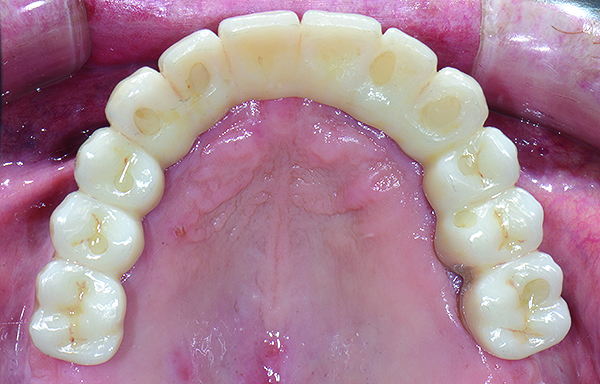

Fig 18. Intraoral occlusal views of maxillary (Fig 18) and mandibular (Fig 19) zirconia restorations at 1.5 years.

Figure 18

The patient has been followed for continuing care since completion of the reconstruction and no complications have been reported to date (Figure 17 through Figure 20).